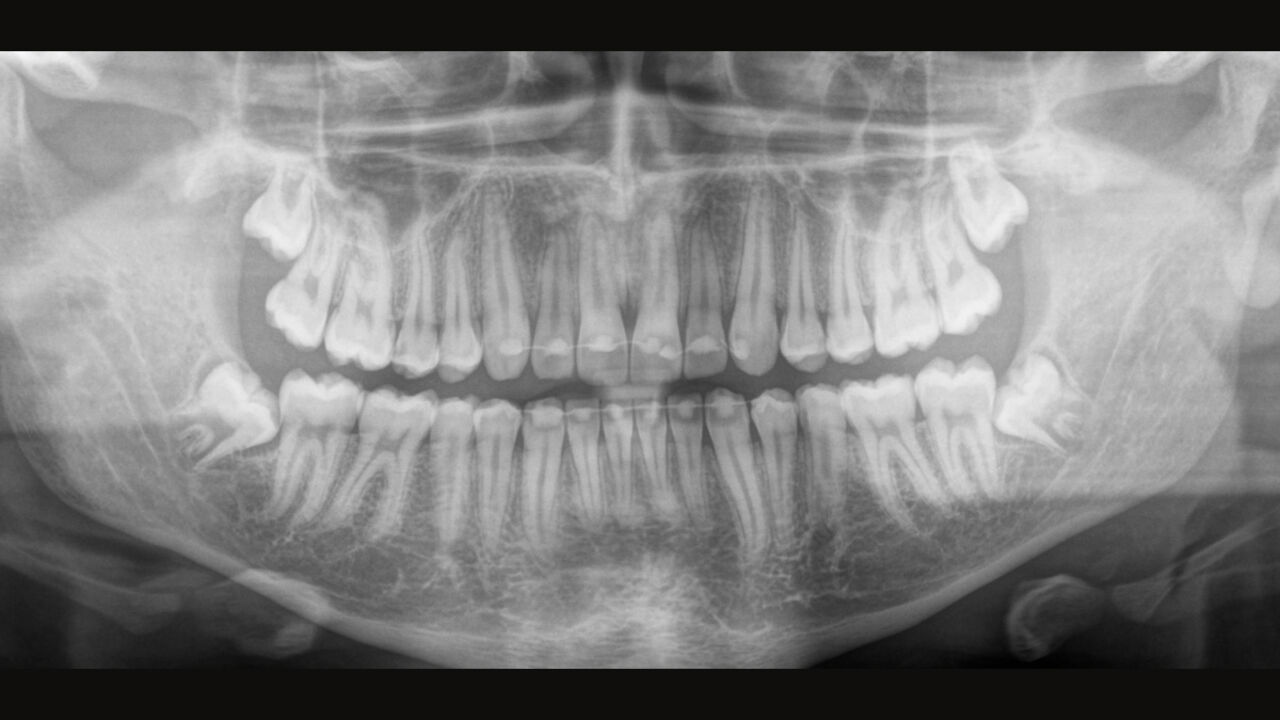

The Direct Conversion Sensor (DCS) has revolutionized the standard of panoramic imaging. X-rays are converted directly into electrical signals. Thus, there is no signal loss due to light conversion, as is the case with conventional systems. The result: images with a high level of sharpness and contrast – even at an extremely low radiation dose. For accurate diagnostic information to support targeted treatment.

The image below shows a panoramic X-ray without and with DCS technology. Using the arrow, drag the control across the image to see the difference the direct conversion sensor makes to the image quality and diagnostic possibilities.

The right focus is crucial for excellent panoramic radiographs. With the autofocus function you will automatically receive an image with the best possible sharpness in focus. Dentsply Sirona Imaging devices take several thousand individual images in one cycle and automatically identify the areas where the jaw is optimally positioned. Without any additional manual steps, these images are then displayed in a final sharp image.